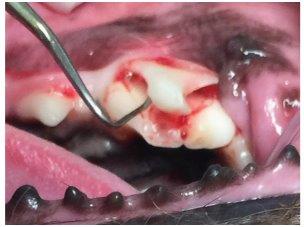

dog tooth probing

Above: A dog’s tooth before probing (Image reproduced with kind permission from Dr Tara Cashman, President of the Australian Veterinary Dental Society).

Below: The same tooth as above after probing. There was minimal tartar present on the tooth before cleaning but there was this very painful fracture present – highlighted by the orange arrow and circle (Image reproduced with kind permission from Dr Tara Cashman, President of the Australian Veterinary Dental Society). This shows the importance of a full dental examination to discover serious dental disease which could otherwise be missed. It also demonstrates the importance of the patient being under anaesthesia so that they are unable to feel pain.